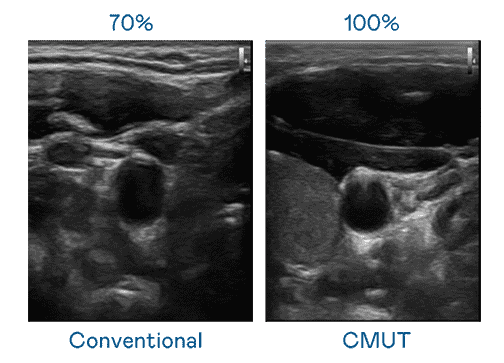

CMUT 技术是一种用电容式微机电元件来产生超音波讯号的技术。。。与传统 PZT 压电式技术相比,,,,CMUT 频宽增加 30%,,,,更宽频的超音波讯号让影像解析度大幅提升,,是实现高影像品质医疗超音波扫描、、、、促进精准医疗发展的关键技术。。。。

大频宽带来超清晰影像

超音波影像的解析度高低,,首先取决于探头能发出的讯号频宽。。william威廉中文官网 CMUT 可提供高清晰的超音波讯号,,,提供高频宽、、、高灵敏度、、、影像纹理细节更高的超音波影像,,,,协助医护人员缩短影像判读时间及利用精准的医疗影像进行诊断。。。